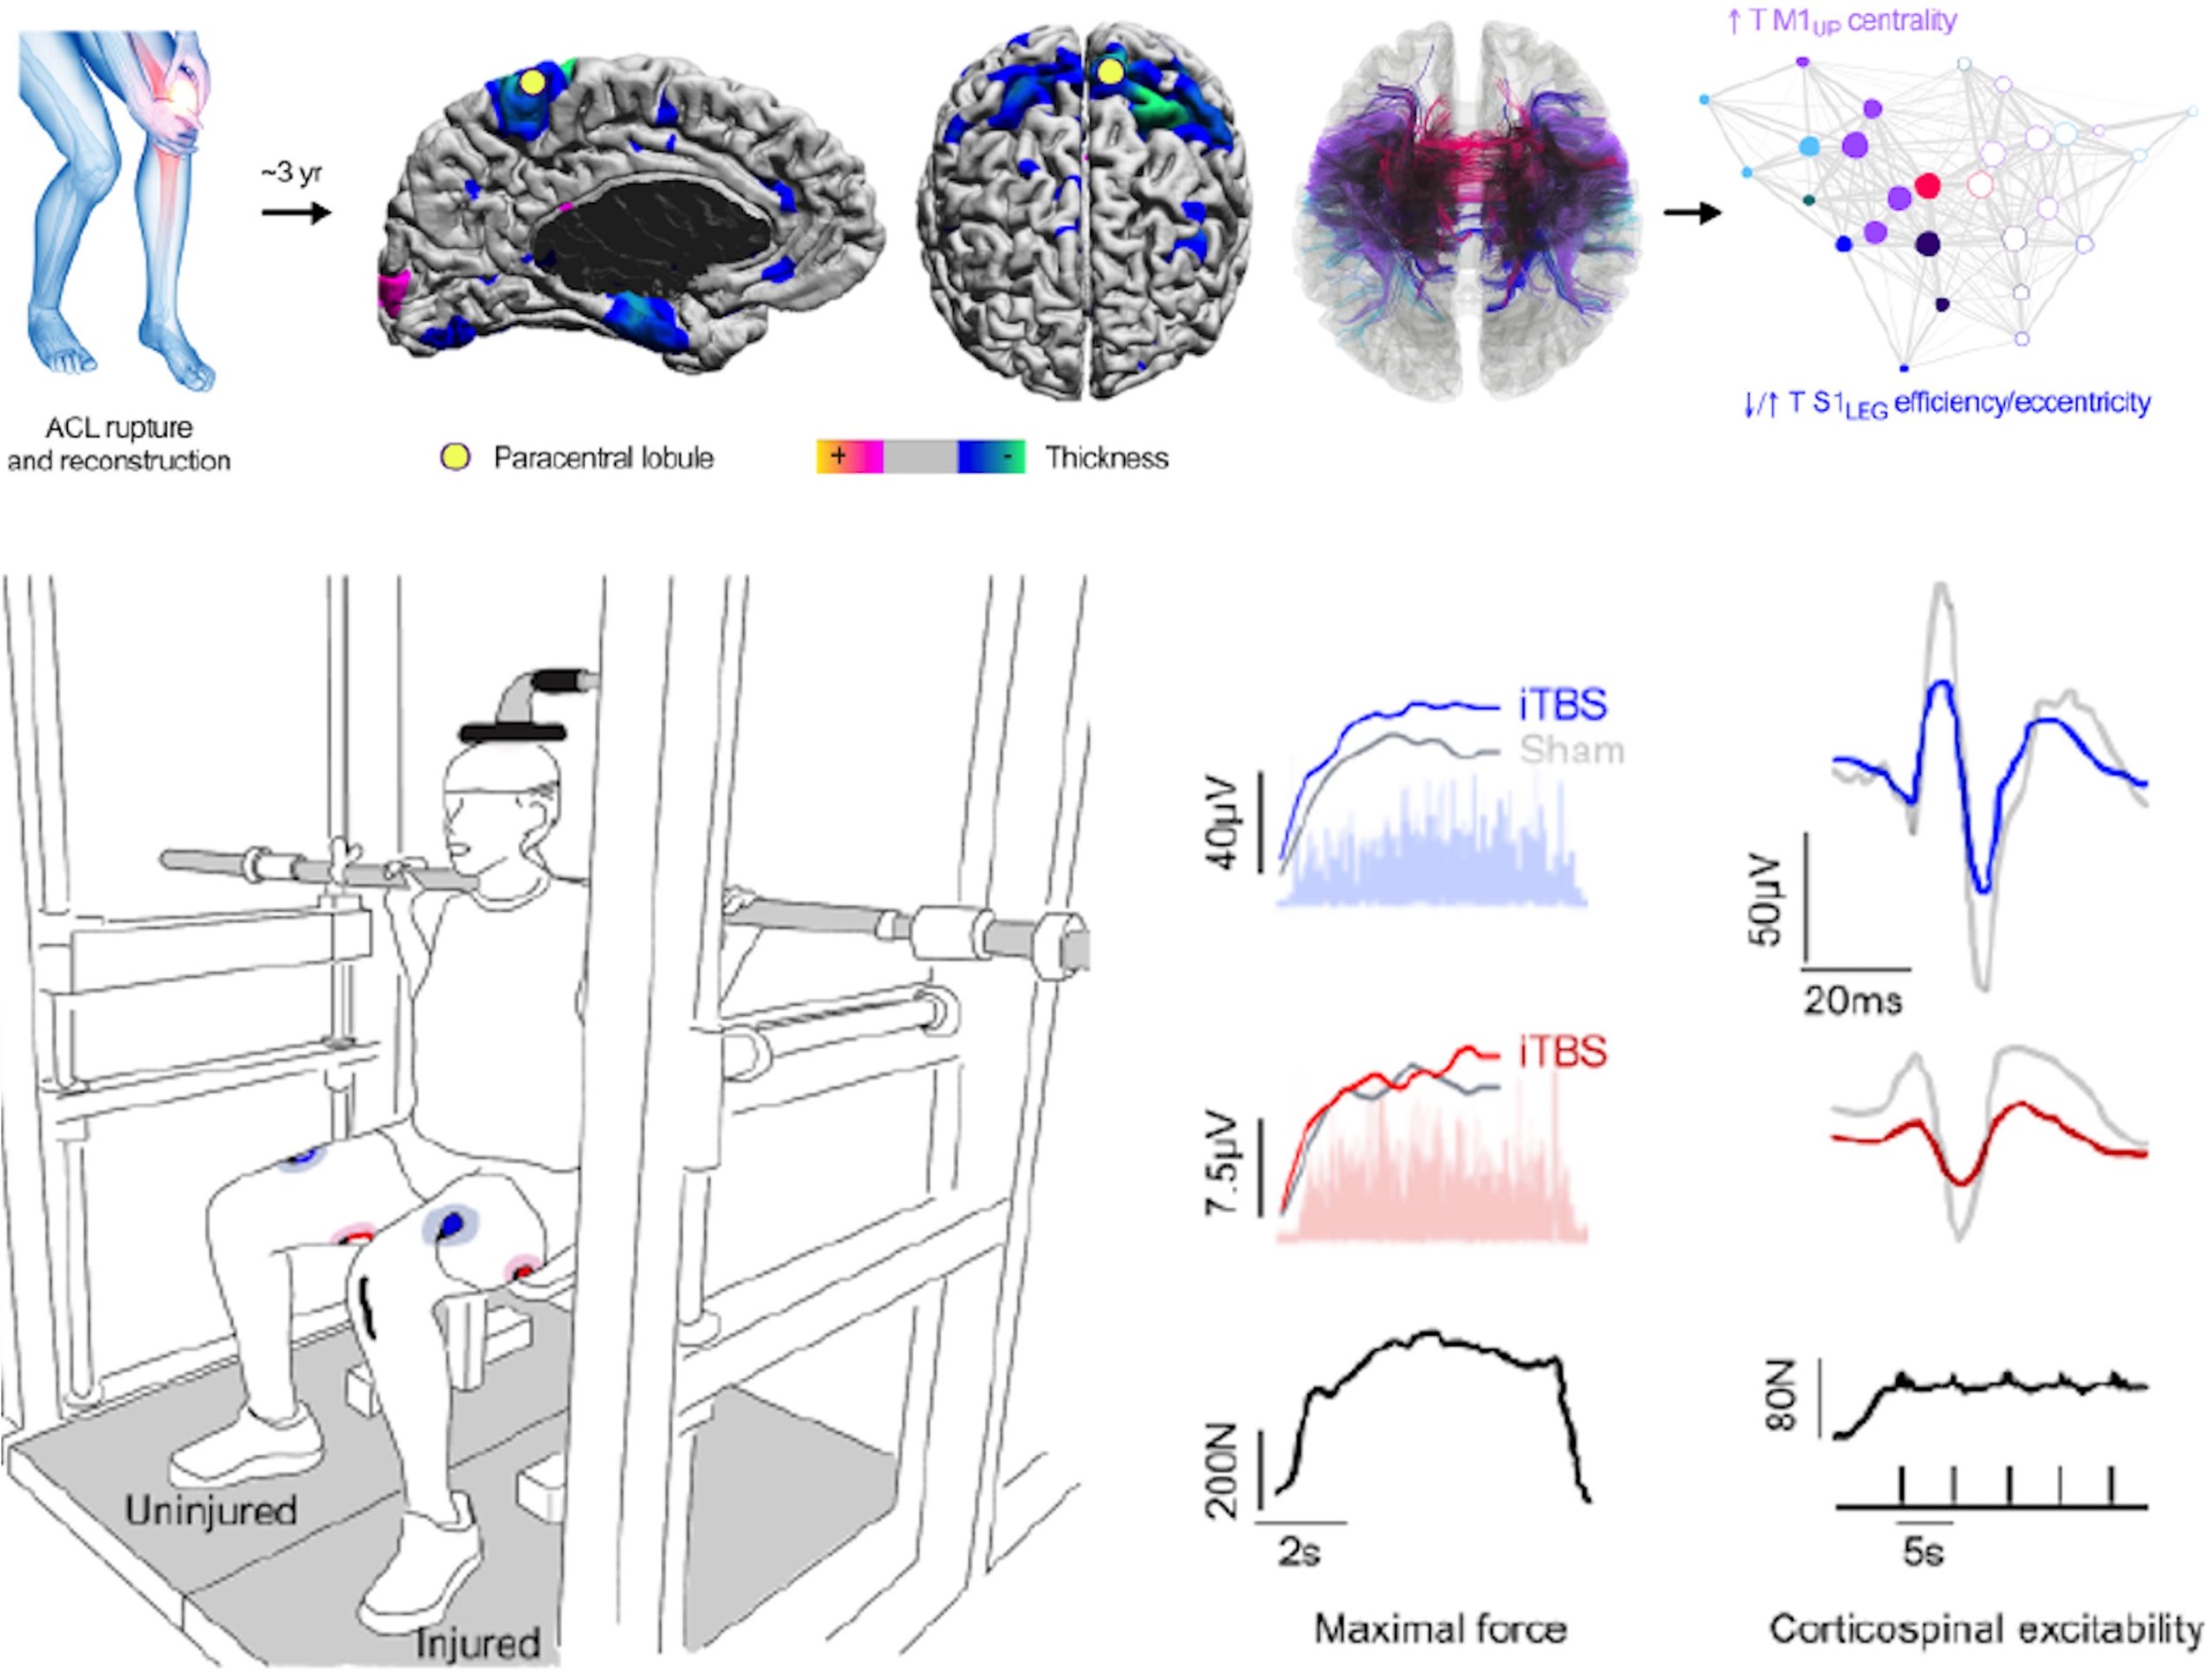

The INBRAIN Laboratory advances human performance through rigorous, innovative, and highly interdisciplinary experimental research. We integrate neuromodulation, multimodal neuroimaging, molecular biology, biomechanics, psychometrics, and wearable sensing to determine how the brain and body adapt to behavior, experience, stress, and injury. Our collaborations across academia, medicine, and the military translate mechanistic insight into actionable approaches that strengthen readiness, enhance recovery, and improve human capability.